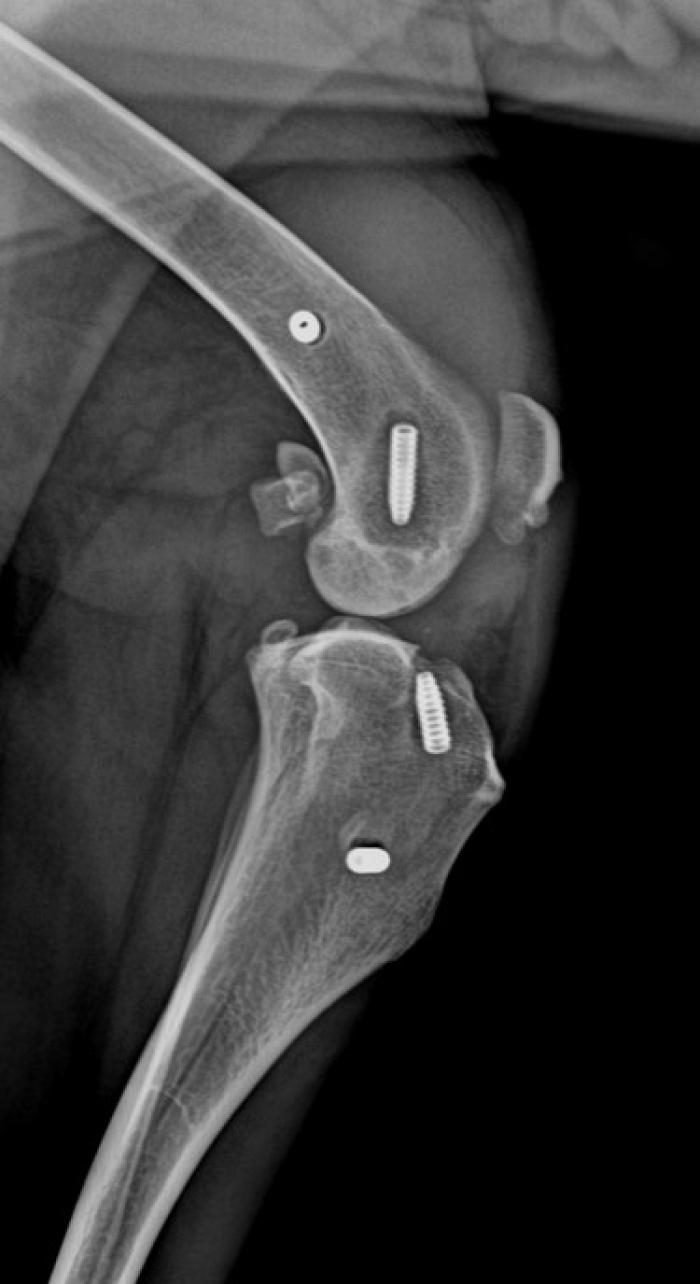

El ligamento de polietileno ultrarresistente de ultra alto peso molecular, se fija mediante tornillos interferenciales de titanio (Figura 2).

- la isometría: colocación de los puntos isométricos,

- las fibras libres: posicionamiento de las fibras libres (Figura 3),

- la tensión a ejercer: regular la tensión que ejerce ese ligamento.

El ligamento “Evolig” tiene una estructura única en el mundo: una parte central activa, compuesta únicamente de fibras longitudinales, llamadas “free fibers” o “fibras libres”. Las fibras libres intraarticulares de Evolig, han hecho que aumentara considerablemente la resistencia a la fatiga ya que, es el primer implante que reproduce la función del ligamento natural. Su diseño permite la máxima biocompatibilidad, integrando los movimientos naturales de torsión, flexión y tensión propios de la articulación.